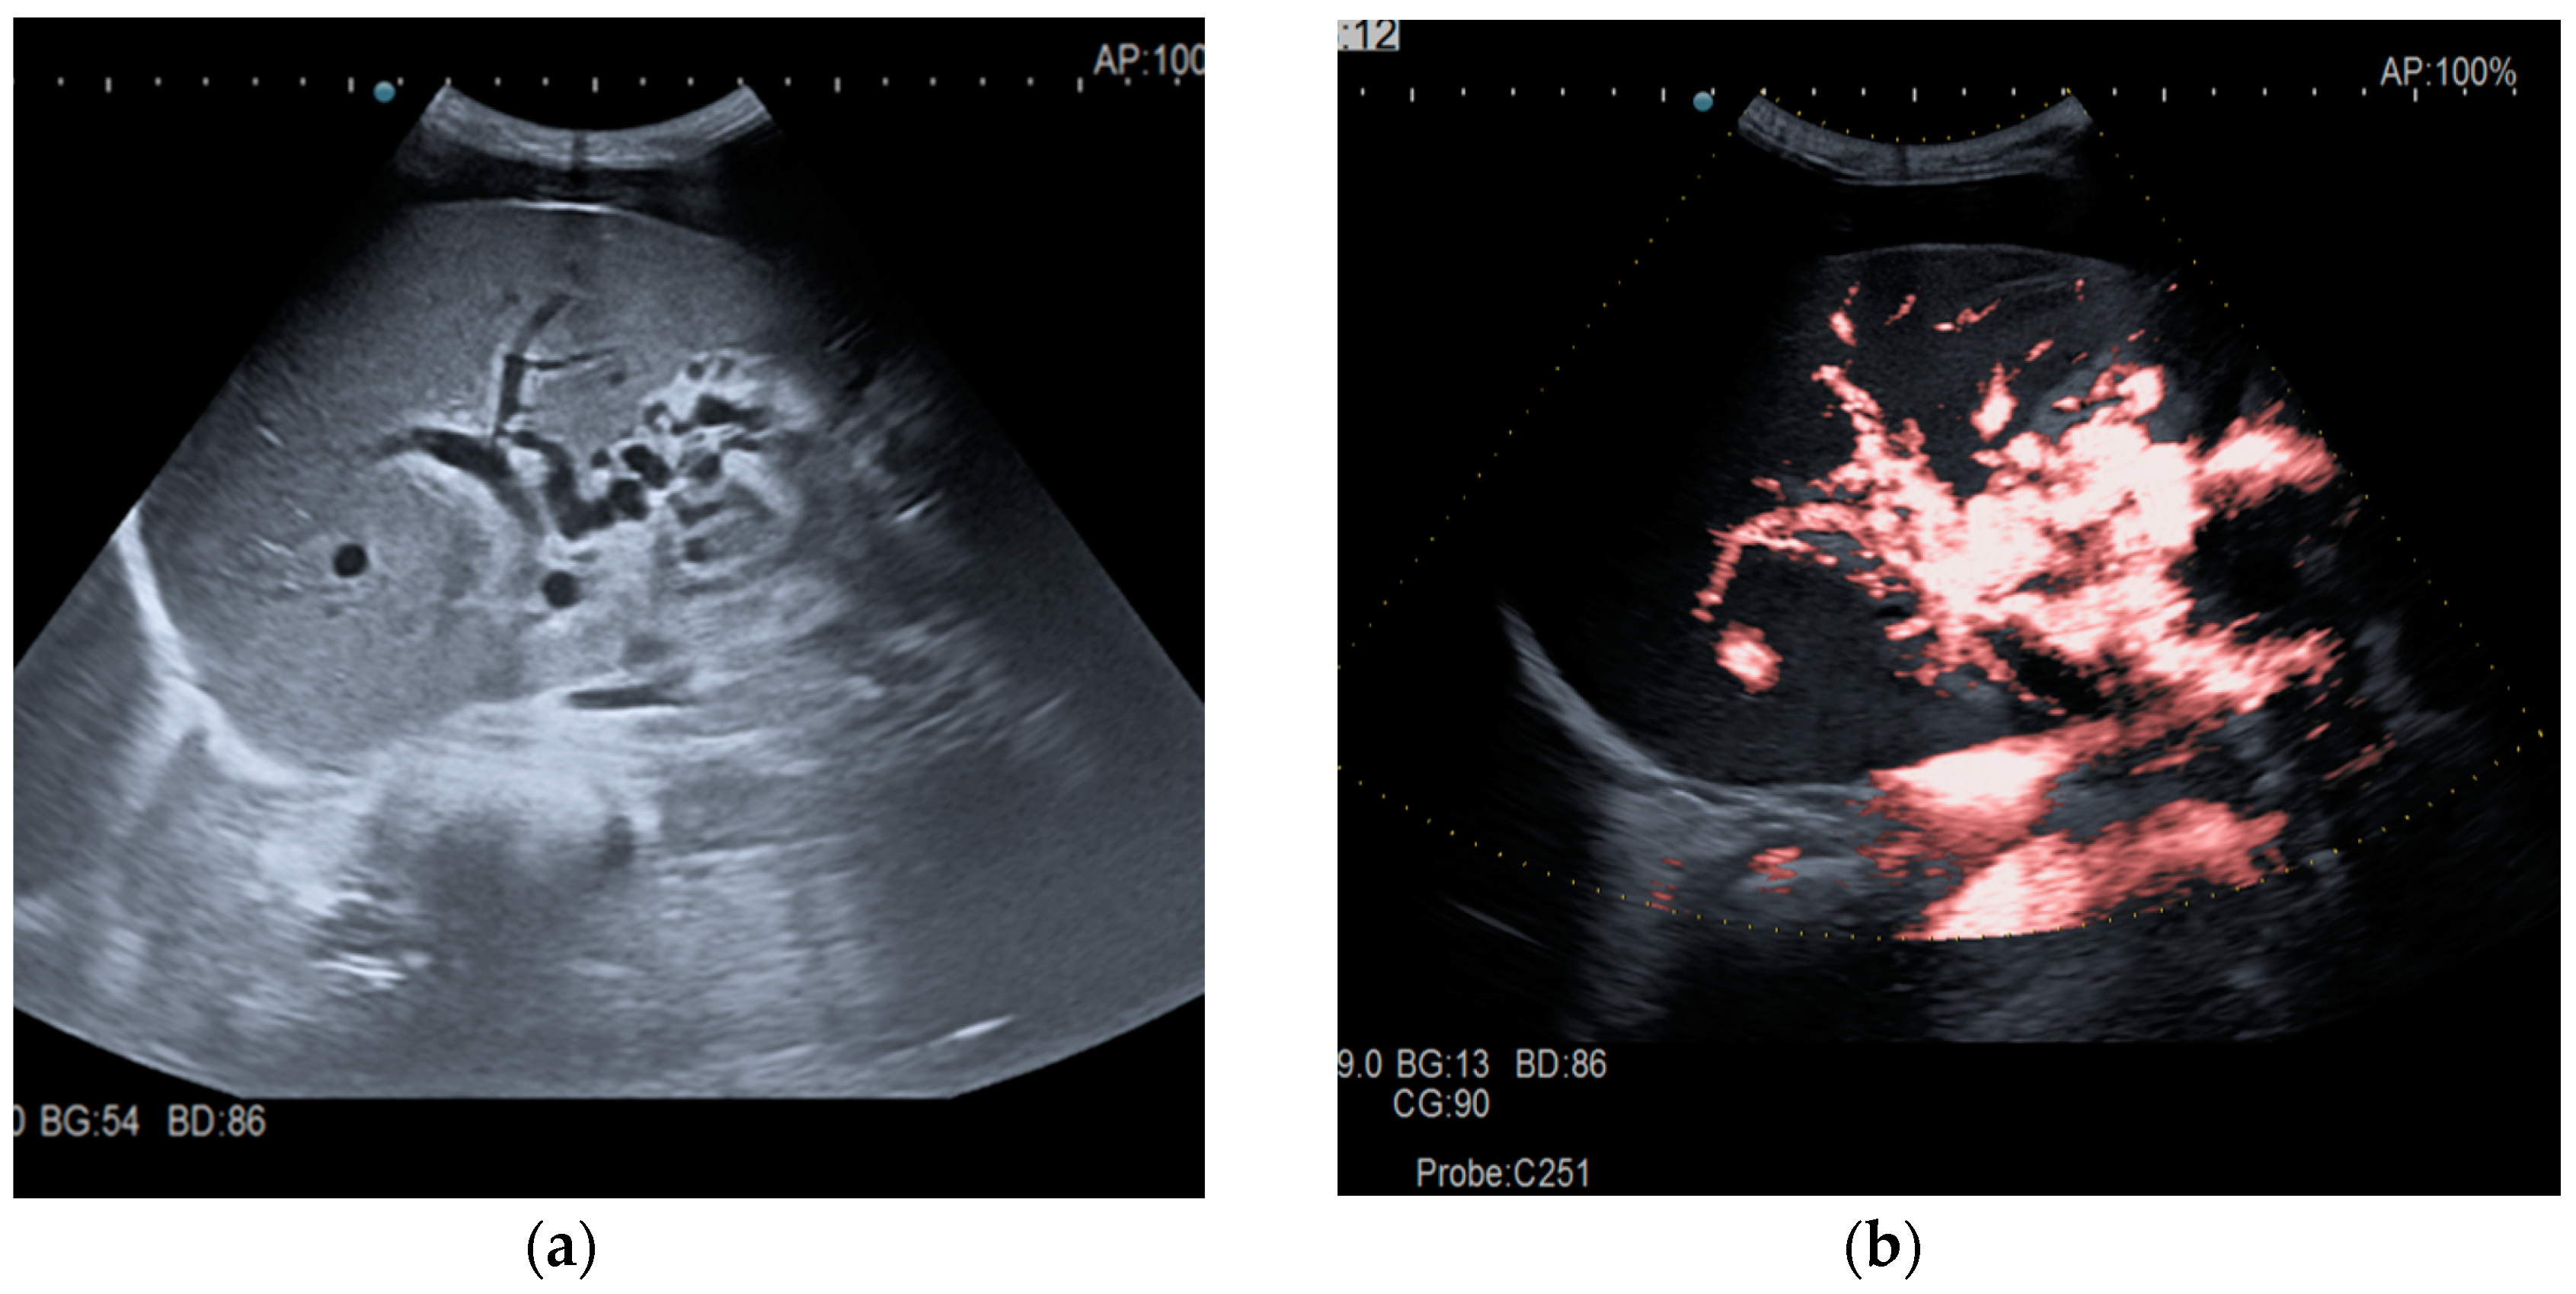

Figure 2.

Portal cavernomatous transformation. (a) Portal vein cannot be identified; instead, meandering venous branches are visible in the porta hepatis, indicating portal vein thrombosis and consequent cavernous transformation. (b) Power Doppler ultrasonography identifies flow within the vessels.

Transabdominal ultrasound with Doppler protocol (Figure 1a,b and Figure 2a,b), CT scan (Figure 3a,b), and MRI (Figure 4a,b) were used for the diagnosis in 88.9, 75.1, and 15% of cases, respectively. CEUS was used for the diagnosis in 49 cases (25.9%) but in only 29 cases was it used for the evaluation of the thrombus, and in two cases for cavernoma diagnosis (Figure 5a,b and Figure 6a,b).